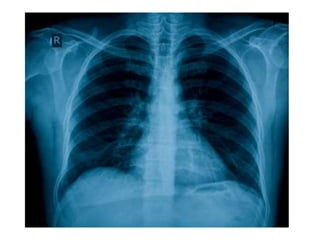

Normal Chest X-Ray

Scheme of viewing PA film

1. Request form                Name ,age, sex, date, clinical information

2. Technical                   View

Centering, patient position

Side Markers

Adequate inspiration

Exposure/Penetrance

3. Soft tissue and bony cage   Subcutaneous emphysema, fractures